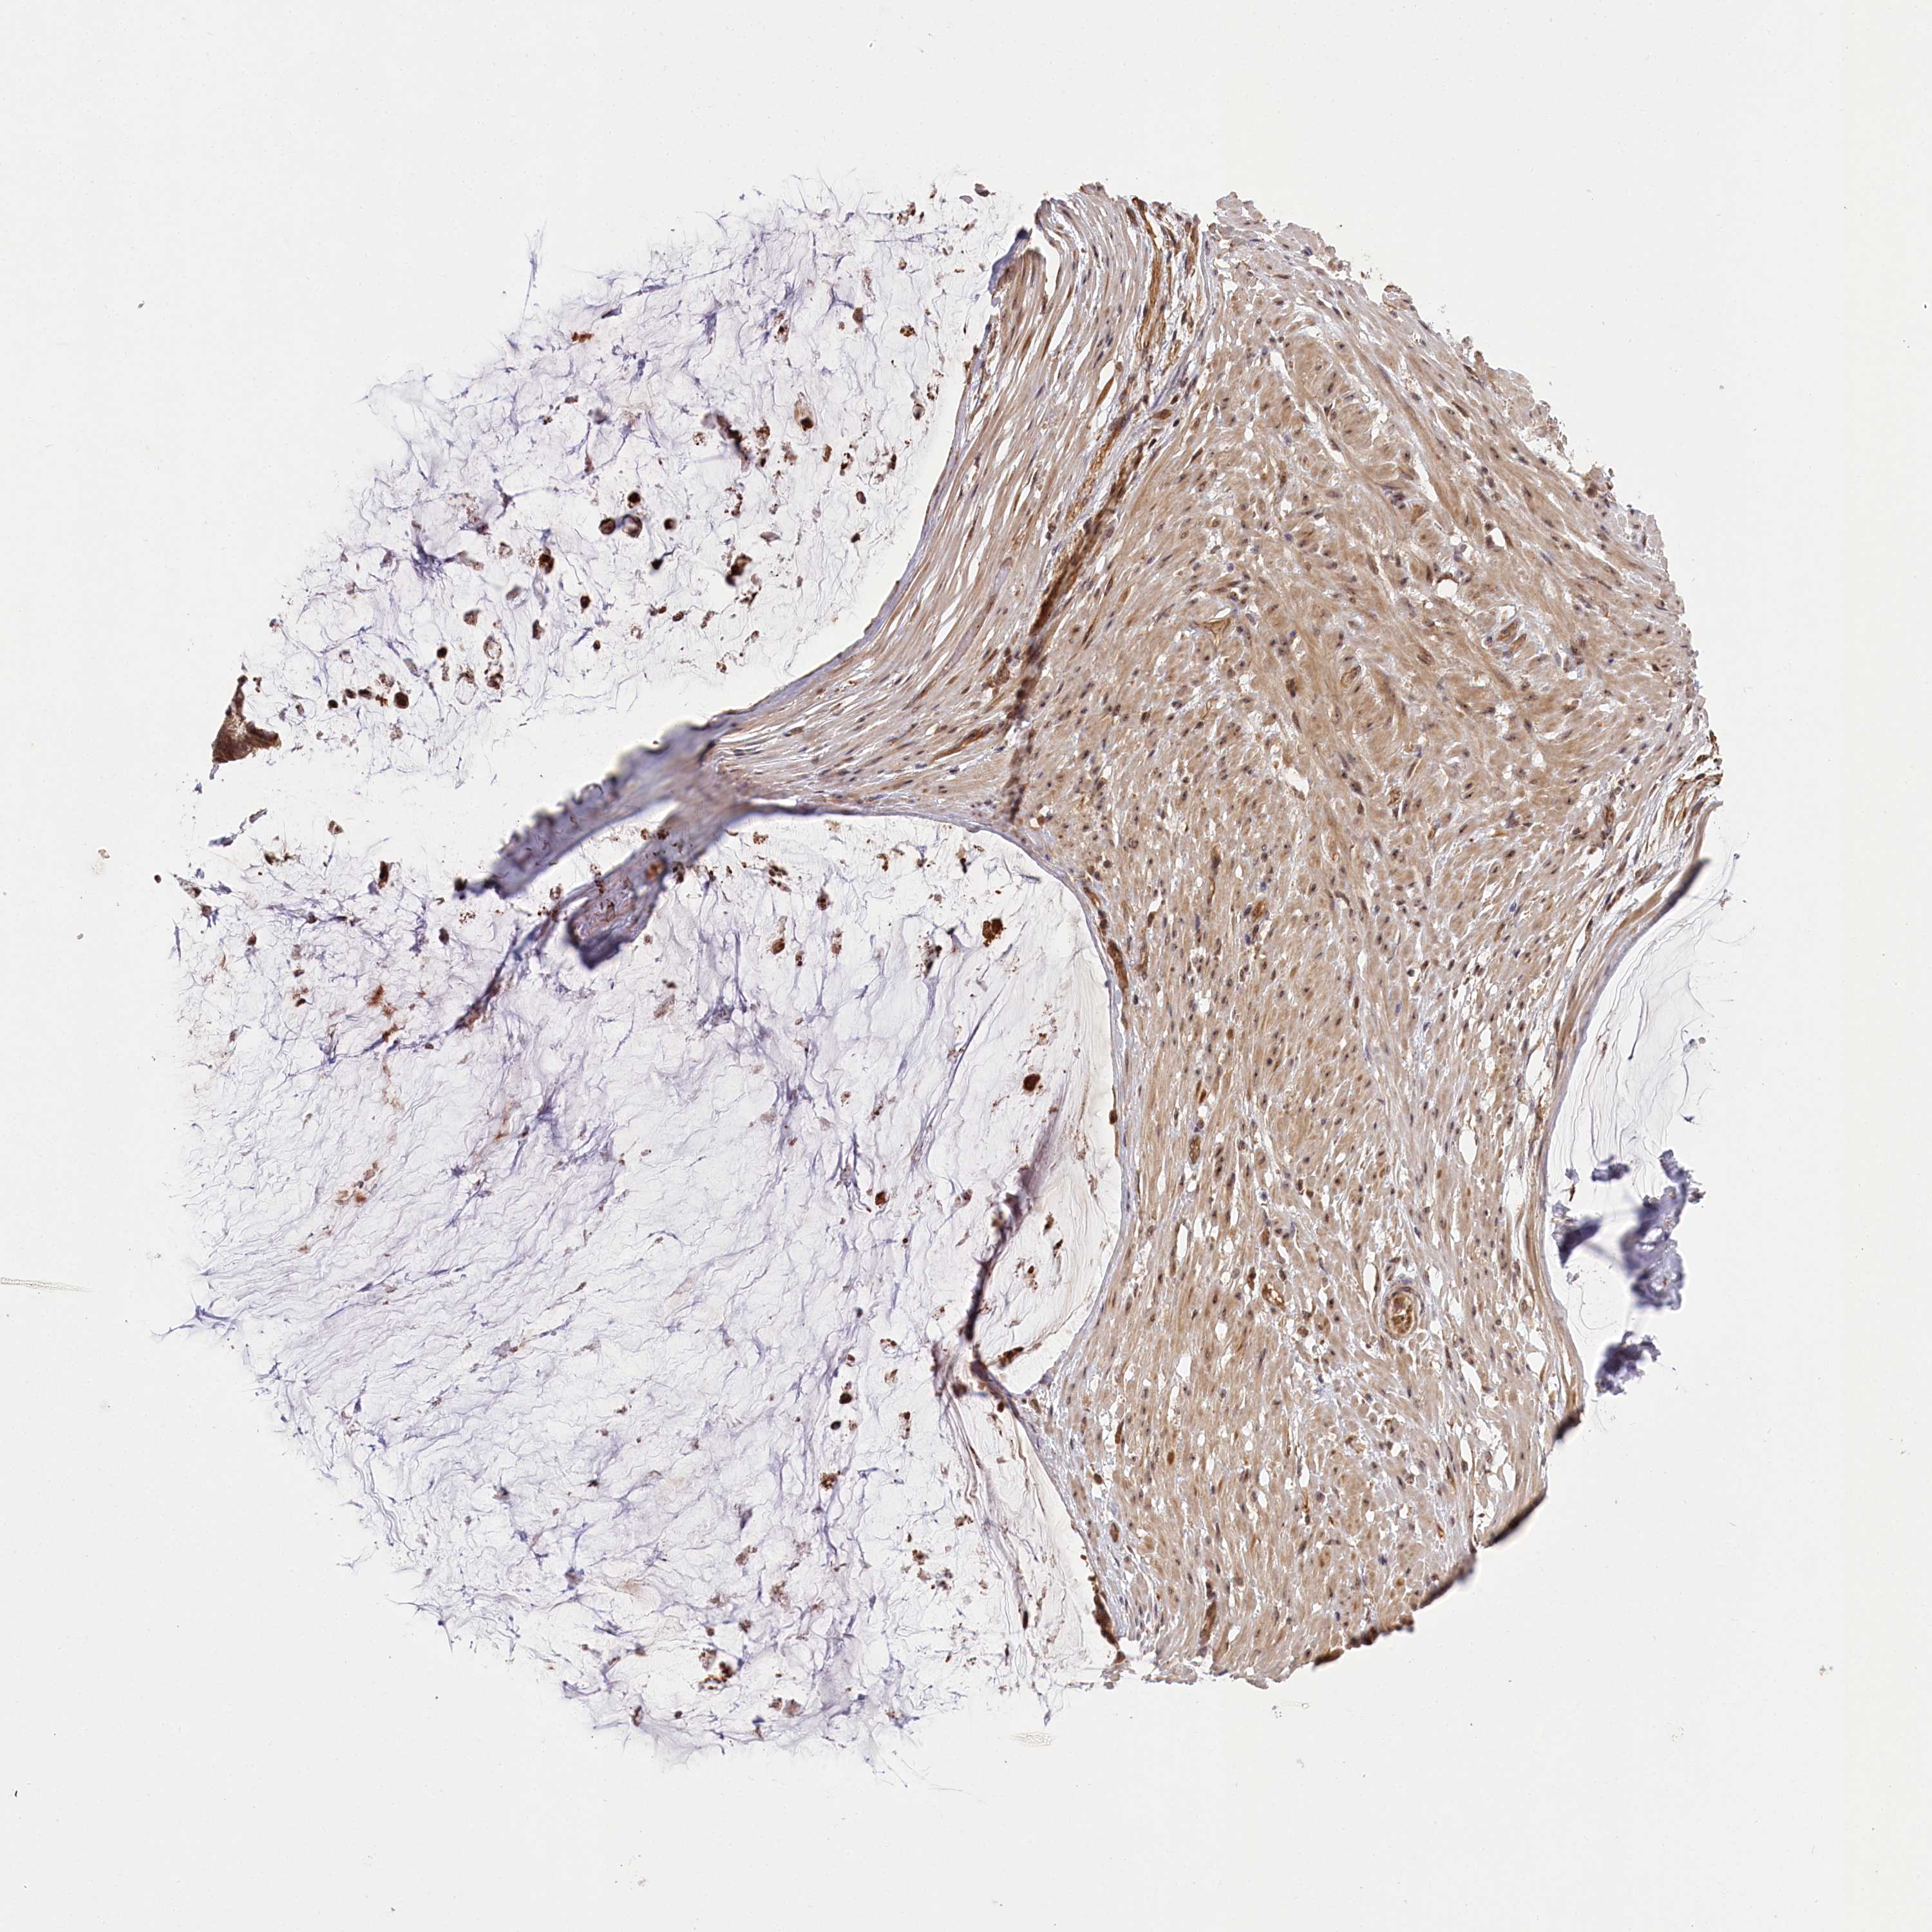

OVARIAN CANCER - Protein expressioni

A mouse-over function shows sample information and annotation data. Click on an image to view it in a full screen mode. Samples can be filtered based on level of antibody staining by selecting one or several of the following categories: high, medium, low and not detected. The assay and annotation is described here.

Note that samples used for immunohistochemistry by the Human Protein Atlas do not correspond to samples in the TCGA dataset.

Antibody stainingi

Antibody staining in the annotated cell types in the current human tissue is reported as not detected, low, medium, or high, based on conventional immunohistochemistry profiling in selected tissues. This score is based on the combination of the staining intensity and fraction of stained cells.

Each image is clickable and will lead to virtual microscopy that enables deeper exploration of all samples and also displays staining intensity scores, fraction scores and subcellular localization as well as patient and tissue information for each sample.

Antibody HPA037811

Antibody HPA037812

Cystadenocarcinoma, serous, NOS

Carcinoma, endometroid

Cystadenocarcinoma, mucinous, NOS

Carcinoma, NOS